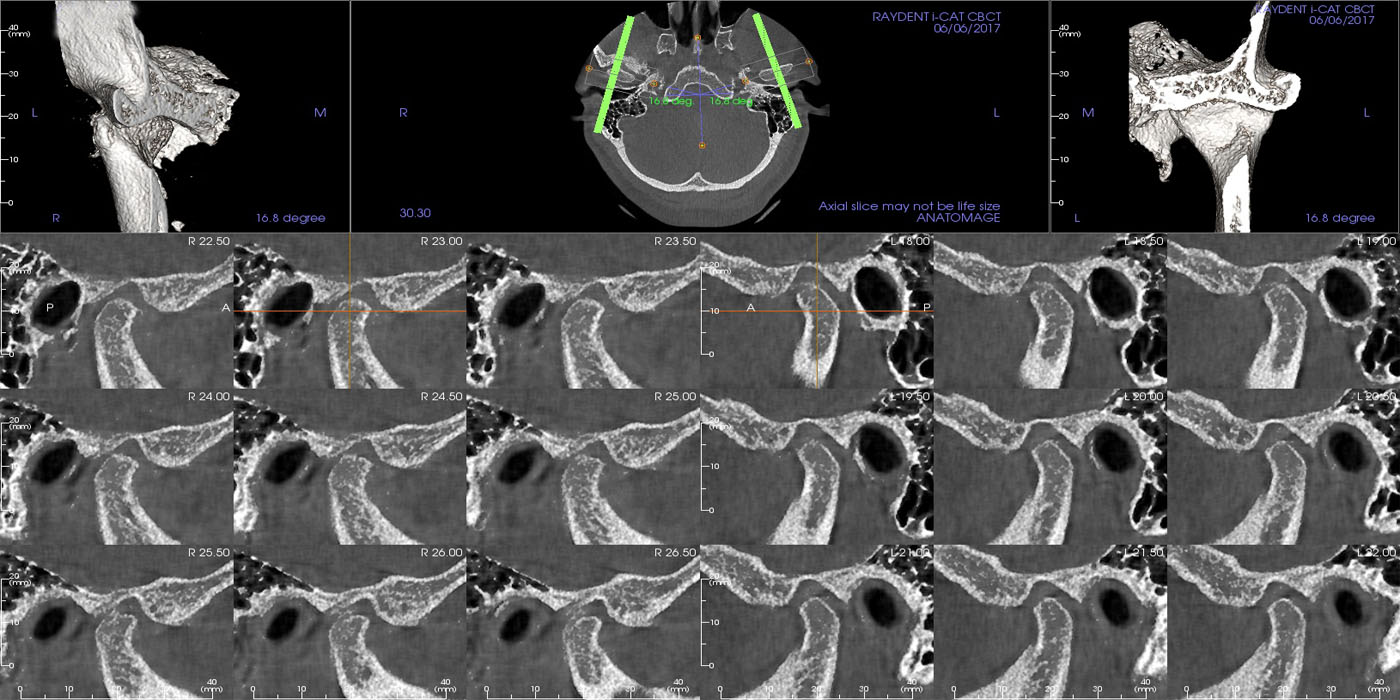

investigations are of paramount importance in the diagnostic assessment of a patient with TMD. Bony changes in the TMJ like flattening, sclerosis, formation of osteophytes, erosion, resorption of the condylar head, erosion of the mandibular fossa and reduced joint space. are the most prevalent degenerative changes seen on CBCT.

TMJ scan can provide 3d image for TMJ which will provide a very close and accurate image for proper diagnosis and evaluation of the joint.